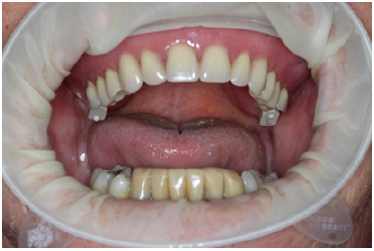

After concluding the surgical phase, the implant scan bodies were connected to the implants and merged together with the universal scan template (Designed by Dr Andrea Papa, produced by LaStruttura S.p.A., Cassano Magnago, Italy), in order to ease the scanning procedure in case of altered or bleeding mucosa (Figure 5). The scan started from the skeletal scan bodies to allow the software to correlate the pre-surgucal and post-surgical scans obtaining a perfect relation with the opposing arch (Figure 6).

In the resulting post-surgical intermaxillary space, a fixed full-arch temporary prosthesis was digitally designed and manufactured in a complete digital workflow (CAD/CAM) with the occlusal plane parallel to the Camper’s plane and the bipupillary plane, it was then screwed on the implants (Figures 7-12). The definitive prosthesis will be fabricated once the implants are integrated and both hard and soft tissue are healed and stable.

Figure 8A: Maxillary arch immediately after surgery before positioning the temporary full-arch prosthesis.

Figure 8B: Temporary maxillary full-arch prosthesis.

Figure 8C: Temporary maxillary full-arch prosthesis screwed on the implants immediately after surgery.